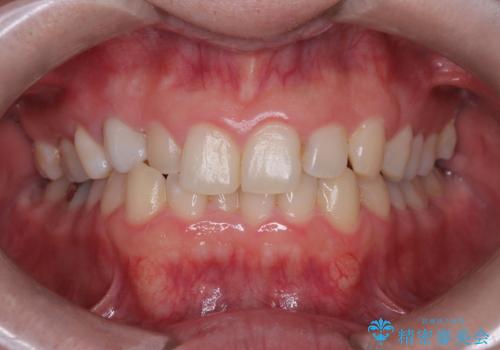

突き出た前歯を下げて理想的な横顔に。上下左右4番抜歯による審美ワイヤー矯正

担当医 河口智英